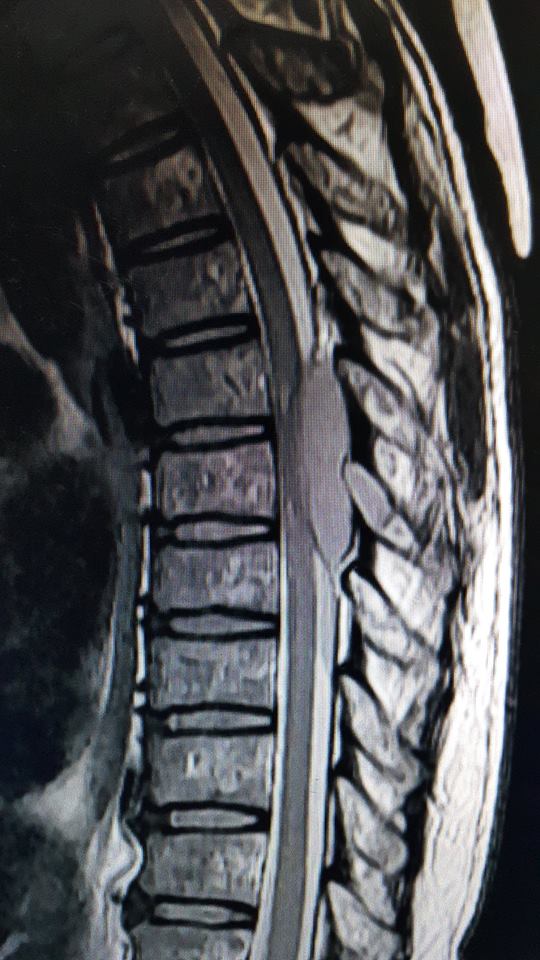

ภาพ MRI แสดงการกดทับของไขสันหลังจากโรคมะเร็ง และภาพเอกซเรย์แสดงการยุบตัวของกระดูกสันหลังจากโรคกระดูกพรุน